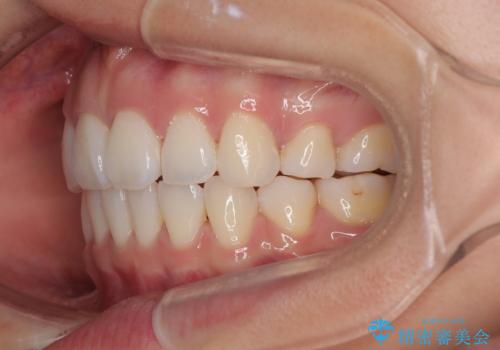

- 前歯が突出して、眠るときに口が開いてしまうことを気にして来院された患者様です。

横から見た際の口元の飛び出した印象も改善したいとのことで、上下左右の第一小臼歯4本を抜歯し、ワイヤー装置にて抜歯矯正を行うこととしました。

舌の突出癖改善のためのトレーニングをしっかりと実践してくださり、2年強の治療期間でしっかりと仕上げることができました。